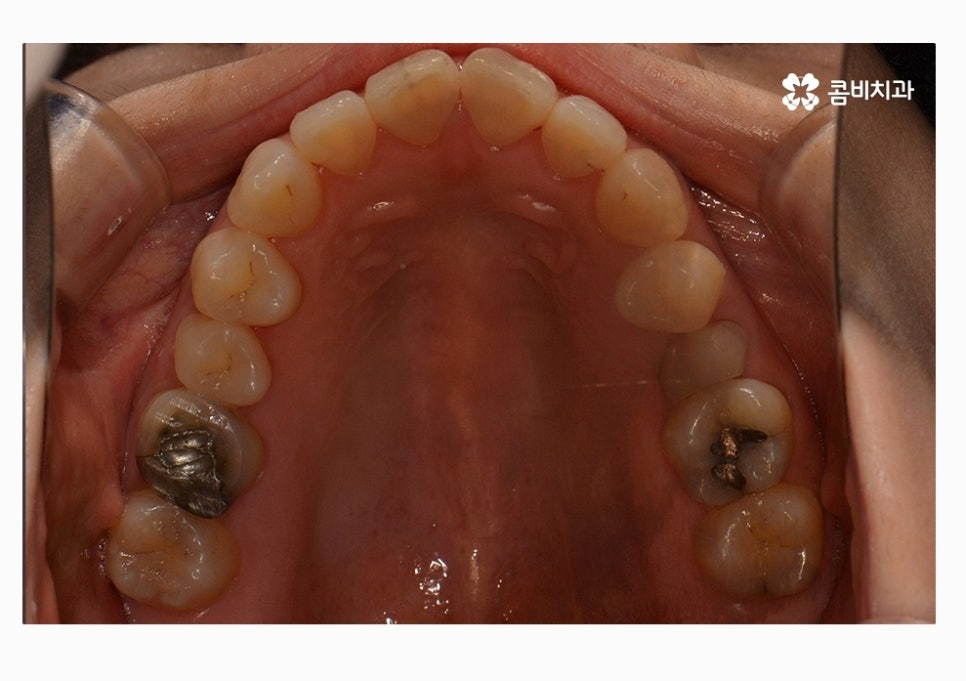

오늘 보시는 콤비교정 치료 케이스가 그러한 경우에 해당하며

정면으로 치열을 볼 때는 비교적 가지런한 편으로

보이지만 자세히 보면 부정교합에 해당한다는 것을 알 수 있어요.

치열 사진을 볼 때 정면보다는 옆모습으로 볼 때

아래 어금니가 위 어금니보다 앞으로 나와있고

앞니 교합이 제대로 맞물리지 않는다는 것이 눈에 띄게 나타나는데